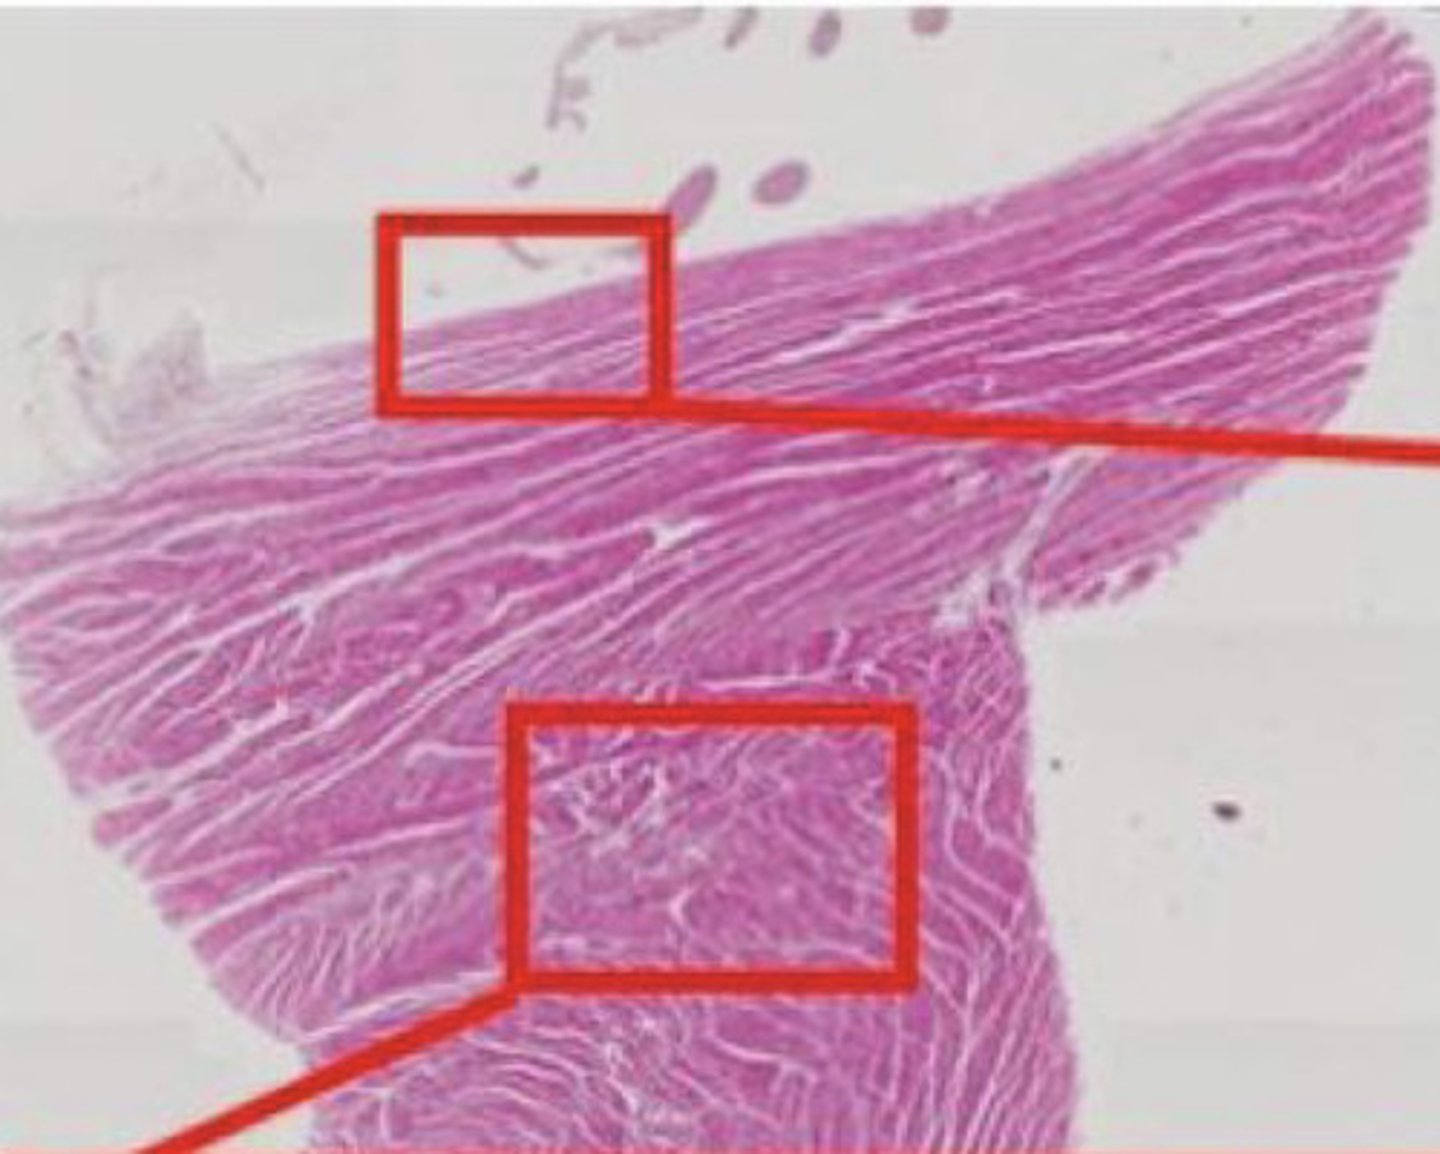

Serce (H+E)